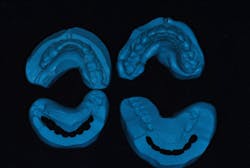

We take a full series of photographs and use a facebow to mount high-quality study models on a semiadjustable articulator in centric relation. Once we have this data, we can begin the treatment-planning process.

As we develop a treatment plan, we do the case four times: (1) in our minds, (2) in wax, (3) in provisionals, and (4) in porcelain.

We will also have started to develop a plan for the best approach to achieve each objective. Once the plan is finalized, we’re ready to move on to wax and translate that mental image into a 3-D reality using wax and stone. There is a specific sequence to this process:

- Place the models on the articulator and complete the wax-up to provide equal intensity stops on all teeth, with anterior guidance that prevents posterior interferences in all directions of mandibular movement.